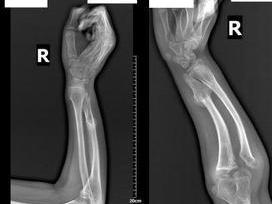

本病男性多于女性,约为3∶1,多见于儿童至20岁左右者。多数病人有阳性家族史,作者医院即有父亲及两个女儿同时住院手术的病例。一般临床表现多为可触及的性肿块。由于骼短缩及弯而造成骼畸关节附近的肿块常可造成关节活动受限。遗传性多发性骨瘤的病变常成对称分布。病变的数量不一,多的有超过100个者。典型发病部位是股骨、胫腓骨的远近侧端及肱骨近侧端(图1,2)。明:如果在膝关节周围上没有外生骨疣,则遗传性多发性骨瘤的诊断不能成立。位于桡、尺骨远侧部的发病稍少些。与单发性骨瘤相比,遗传性多发性骨瘤更倾向于在、髂肋骨处发病。

这种病的很大特点在于有成的缺陷和骼畸。特是在髋部可呈双侧髋外翻及股骨近侧端变宽(图3)。腕关节出现逐渐的尺骨偏斜、尺骨相对短缩等。